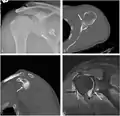

CT scan showing a bony Bankart lesion at the antero-inferior glenoid

3-D CT reconstruction of a bankart lesion which occurred post anterior shoulder dislocation. This subject's humerus remains mildly superiorly subluxated. Fracture marked by a black arrow.

Bony Bankart